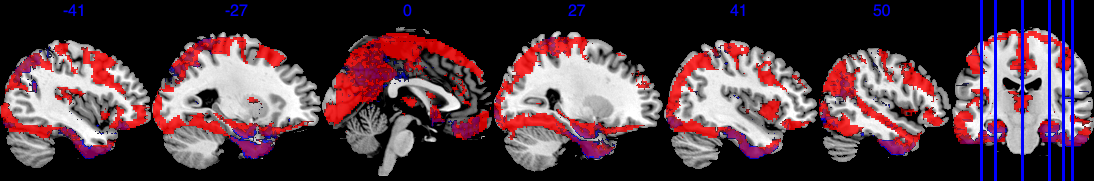

To define the analysis mask, we recall the definition of observed proportion (OP) at location to be , where is the set of all observed locations for individual . We define the group analysis mask as , i.e., the area where each voxel has at least 50% observed data. As shown in Figure 2, the group analysis mask with completely observed data (purple area) covers significantly less area compared to , which has at least 0.5 observed proportion (blue area). In the complete observed data, large portions of the brain regions are missing, notably including the orbitofrontal cortex, the inferior temporal cortex, and the amygdala—regions crucial for emotion processing. In particular, the mask with complete observed data contains only 52 out of the 110 regions in the Harvard-Oxford atlas.

For a visual representation, Figure 3(a) shows the voxel level PIP in the sagittal plane. The highlighted red regions represent voxels with greater than 0.95 PIP. Figure 3(b) presents the effect size of , with the highlighted area in the range . Note that from Figure 3(b), voxels with PIP greater than 0.95 also correspond to voxels with a larger absolute value of effect size. We notice that the activation region (defined by voxel level PIP greater than 0.95) has a negative effect . This can also be validated by the scatter plot in Section D in the Supplementary Material, where the image intensity generally has a negative association with age across all individuals.

Based on our results, we have the following general interpretations: (i) when controlling for the confounders, age has a negative impact on the neural activity for emotion-related tasks; (ii) the negative effect reflected from each voxel is of very small scale, shown as in Figure 3(b), indicating a very low voxel level signal-to-noise ratio; (iii) the top 5 brain regions with the highest RLAR are (a) right intracalcarine cortex, right supracalcarine cortex, and left Temporal fusiform cortex, anterior division, all considered as critical areas for high-level visual processing including face recognition; (b) left temporal fusiform cortex, anterior division, a key structure for face perception, object recognition, and language processing (Weiner and Zilles, 2016); and (c) right inferior temporal gyrus, anterior division, an area for language and semantic memory processing, visual perception, and multimodal sensory integration (Onitsuka et al., 2004). These top 5 regions are also consistently identified in the sensitivity analysis when using half of the data as training data, see Section 4.4.1.